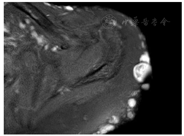

行磁共振左肩关节平扫(图2)示:左侧肩关节表皮可见多发结节状长T2信号,左侧肩胛骨可见小片状稍长T2信号,肱骨内可见类圆形长T2信号。左侧肩关节滑膜囊内、喙突下可见少量条片状长T1长T2信号。左侧冈上肌肌腱可见斑片状稍长T2信号,左侧肩关节肱二头肌长头腱周围可见液体信号影。诊断提示左侧肩胛骨骨髓水肿。左侧肱骨内小囊变。左肩关节滑膜囊、喙突下滑膜囊少量积液。左侧冈上肌腱信号增高,不除外损伤。左侧肩关节肱二头肌长头腱腱鞘少量积液。